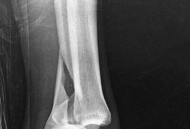

Partial articular fractures, classified under the AO/OTA alphanumeric system as Type B fractures, represent a complex subset of orthopedic injuries where a portion of the articular surface is disrupted while the remainder of the joint remains in continuity with the metaphyseal and diaphyseal regions. The fundamental objective in the surgical management of these fractures is the restoration of articular congruity and the provision of absolute stability to permit early, active mobilization. Unlike extra-articular or diaphyseal fractures where relative stability and secondary bone healing via callus formation are acceptable, partial articular fractures demand anatomic reduction and primary bone healing to mitigate the risk of post-traumatic osteoarthritis.

The epidemiology of partial articular fractures exhibits a classic bimodal distribution. High-energy trauma, such as motor vehicle collisions and falls from significant heights, predominantly accounts for these injuries in the younger, active demographic. In this cohort, fractures are frequently characterized by severe soft tissue compromise, marked displacement, and significant comminution (e.g., split-depression tibial plateau fractures or high-energy pilon variants). Conversely, low-energy mechanisms, typically ground-level falls, are responsible for partial articular fractures in the elderly population. This demographic presents unique challenges, including osteopenia or osteoporosis, which compromises implant purchase and increases the propensity for articular impaction and secondary subsidence.